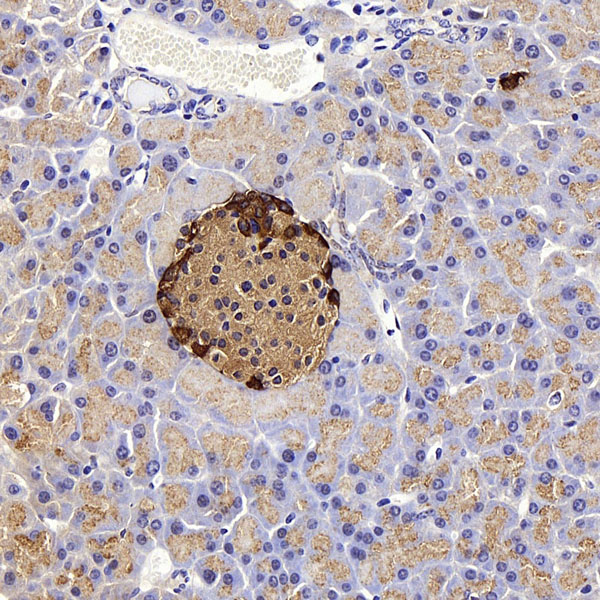

IHC (Immunohistochemistry)

(Immunohistochemistry analysis of paraffin-embedded mouse pancreas using GCG Polyclonal Antibody at dilution of 1:300.)